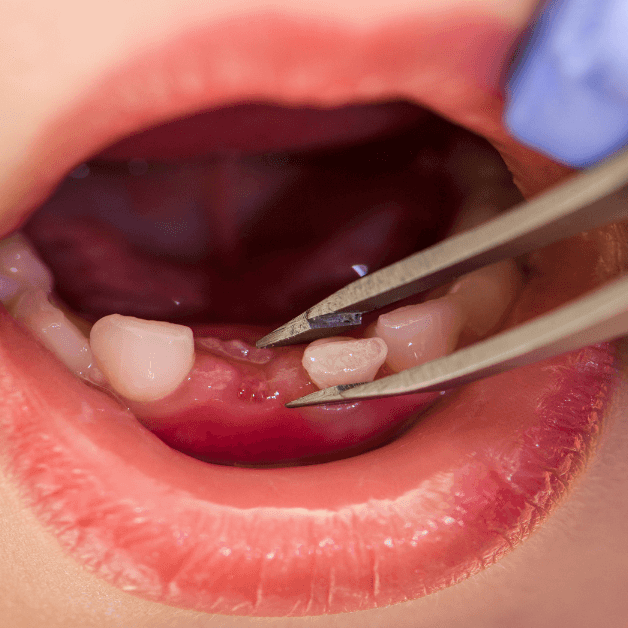

Prosedur pengangkatan gigi yang rusak atau bermasalah secara aman dan profesional.